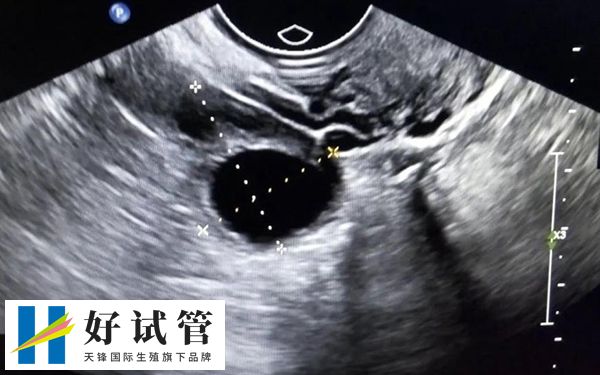

试管婴儿通常在女性双侧卵巢取卵,因为卵巢是女性的生殖器官,其主要功能之一是产卵。女性做取卵手术时,医生会从阴道后穹窿拿一根长长的穿刺针进入盆腔。在超声波的指导下,穿刺针到达卵巢,针对卵泡取卵。

卵巢的正常位置应该在子宫两侧,而少部分患者可能存在盆腔炎症和粘连,卵巢的位置发生了改变,有的紧贴盆腔内大血管,有的位于子宫顶上,平时做超声监测卵泡时,位置不太好找,取卵时可能会给医生增加难度。